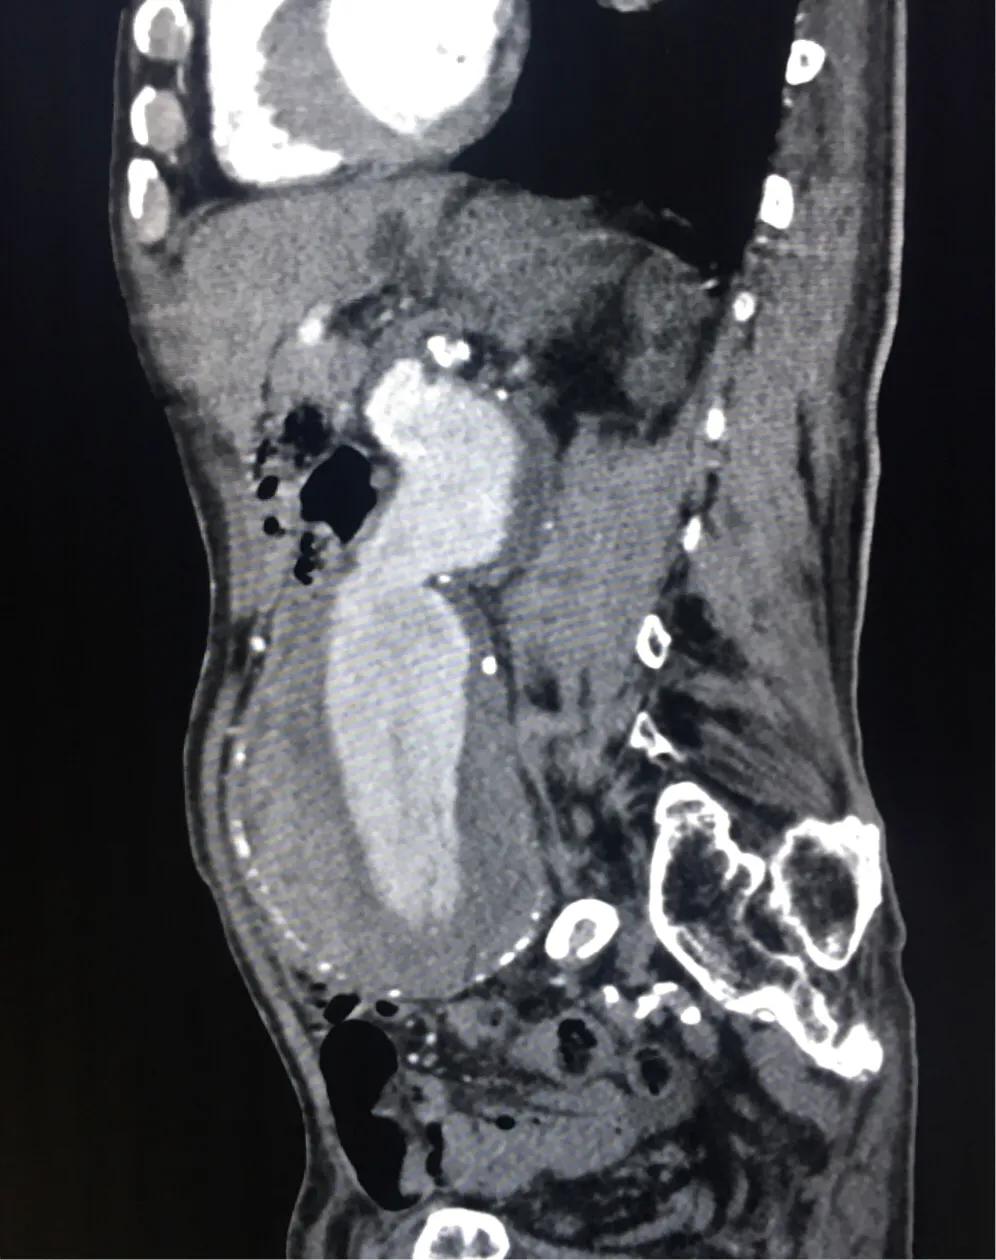

腹部CT明确,腹主动脉瘤样扩张,范围较大,最大横径接近快10厘米了,管壁可见不强化的血栓形成,诊断腹主动脉瘤。

- 真性动脉瘤主动脉局限性扩张或膨凸,附壁血栓表现为新月形或环形充盈缺损